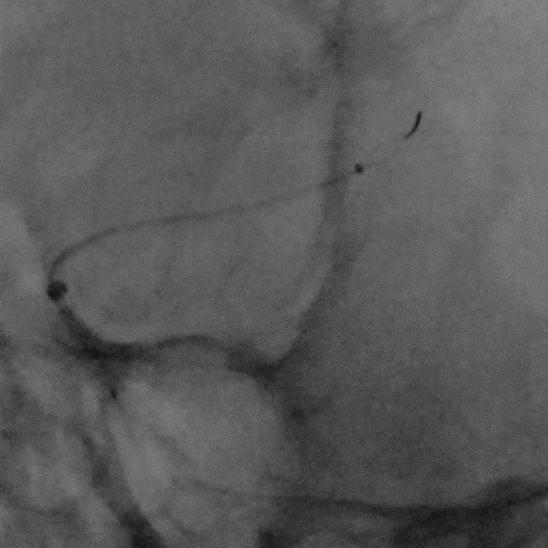

5F 125cm Sim2造影导管携5.5F Introsky X导管鞘成袢后超选左侧ICA。

什么叫桡鞘【例久弥新】寻道于桡——瑞康通5.5F Introsky X导管鞘经桡取栓一例_https://www.jmylbn.com_新闻资讯_第13张

泥鳅导丝、SIM2造影导管、5.5F Introsky X导管鞘同轴下继续跟进,尽可能高到位,随后引入V-18导丝。